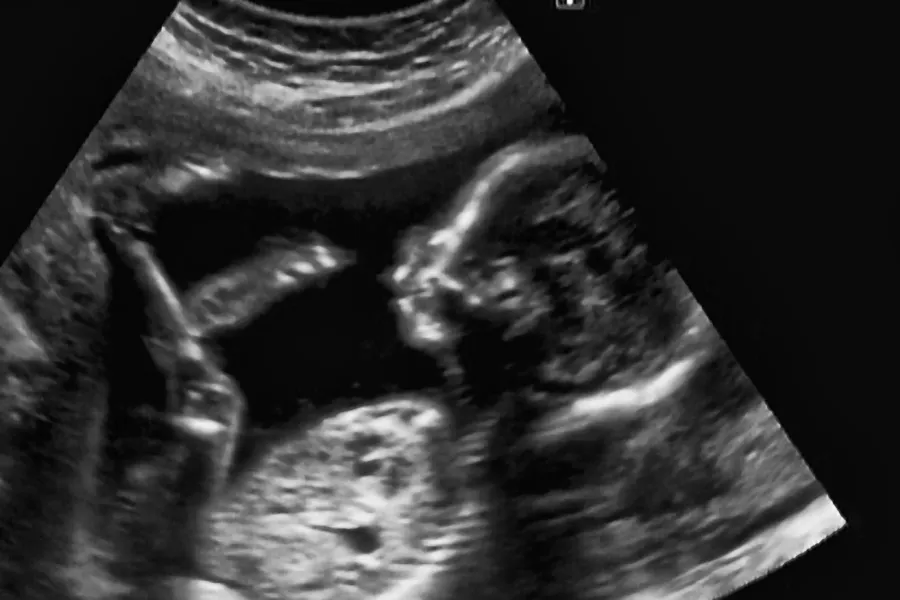

UNN klarer likevel å tilby tidlig ultralyd

Ekstra bemanning gjør at UNN Tromsø likevel klarer å opprettholde tilbudet om tidlig ultralyd for gravide under 35. Kvinner som tidligere har fått avslag på timer i uke 29, blir nå kontaktet.